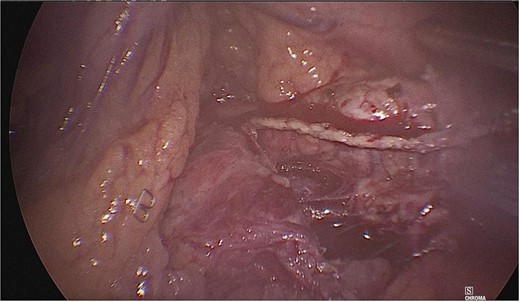

A tumor measuring ~1.5 × 2 cm was identified at the junction of the body with the tail of the pancreas, and dissection of the mesenteric vessels and portal vein was continued. Subsequently, the splenic vein and artery were dissected from the medial to lateral direction at a distance of 2–3 cm. Once released, the neck of the pancreas was divided with an Endo GIA 60 mm endoscopic stapling device (Fig. 3), and a second stapling was performed with an Endo GIA 45 mm (Fig. 4).

The neck of the pancreas was divided using an Endo GIA 60 mm endoscopic stapling device.